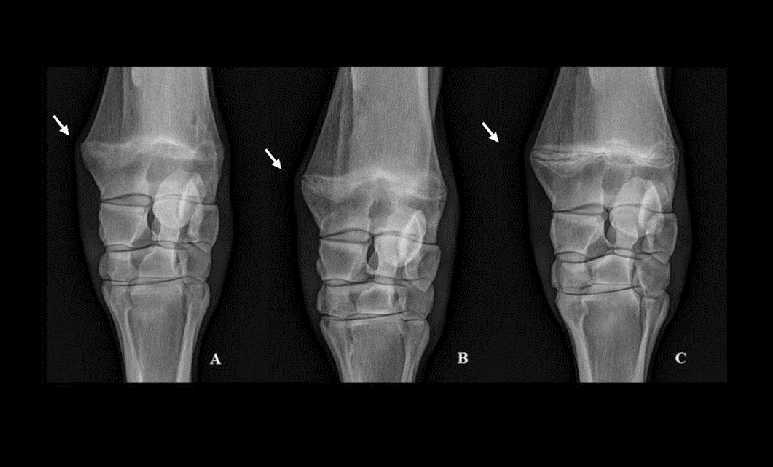

Adams (1974), classified as 'A' when the epiphyseal line is completely calcified, 'B' when the center of the epiphyseal line is calcified but not its periphery, and 'C' if there is no perceptible calcification on the epiphyseal line.

Left (open): Wide physis line separating metaphyseal flare from proximal carpus - classic 'open knee' appearance in a young racehorse. Right (closed): No visible physis, bone is continuous. Indicates skeletal maturity and readiness for training.